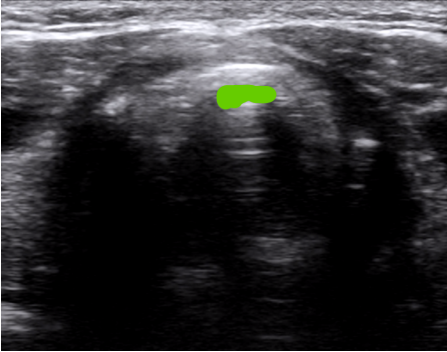

如果选择横切面,则环状软骨为拱形。图8中绿色区域为环甲膜结构。

图片

图8  横向扫查环甲膜平面